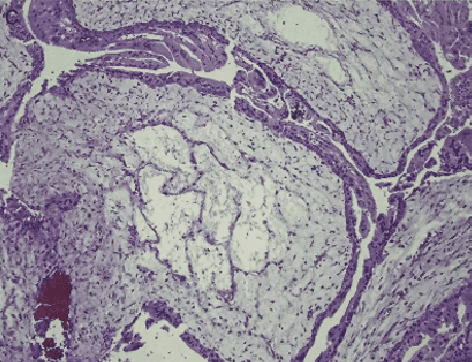

Abstract:Pathological morphology diagnosis is the standard diagnosis method of hydatidiform mole. As a disease with malignant potential, the hydatidiform mole section of hydrops lesions is an important basis for diagnosis. Due to incomplete lesion development, early hydatidiform mole is difficult to distinguish, resulting in a low accuracy of clinical diagnosis. As a remarkable machine learning technology, image semantic segmentation networks have been used in many medical image recognition tasks. We developed a hydatidiform mole hydrops lesion segmentation model based on a novel loss function and training method. The model consists of different networks that segment the section image at the pixel and lesion levels. Our compound loss function assign weights to the segmentation results of the two levels to calculate the loss. We then propose a stagewise training method to combine the advantages of various loss functions at different levels. We evaluate our method on a hydatidiform mole hydrops dataset. Experiments show that the proposed model with our loss function and training method has good recognition performance under different segmentation metrics.

Abstract:As a disease with malignant potential, hydatidiform mole (HM) is one of the most common gestational trophoblastic diseases. For pathologists, the HM section of hydrops lesions is an important basis for diagnosis. In pathology departments, the diverse microscopic manifestations of HM lesions and the limited view under the microscope mean that physicians with extensive diagnostic experience are required to prevent missed diagnosis and misdiagnosis. Feature extraction can significantly improve the accuracy and speed of the diagnostic process. As a remarkable diagnosis assisting technology, computer-aided diagnosis (CAD) has been widely used in clinical practice. We constructed a deep-learning-based CAD system to identify HM hydrops lesions in the microscopic view in real-time. The system consists of three modules; the image mosaic module and edge extension module process the image to improve the outcome of the hydrops lesion recognition module, which adopts a semantic segmentation network, our novel compound loss function, and a stepwise training function in order to achieve the best performance in identifying hydrops lesions. We evaluated our system using an HM hydrops dataset. Experiments show that our system is able to respond in real-time and correctly display the entire microscopic view with accurately labeled HM hydrops lesions.